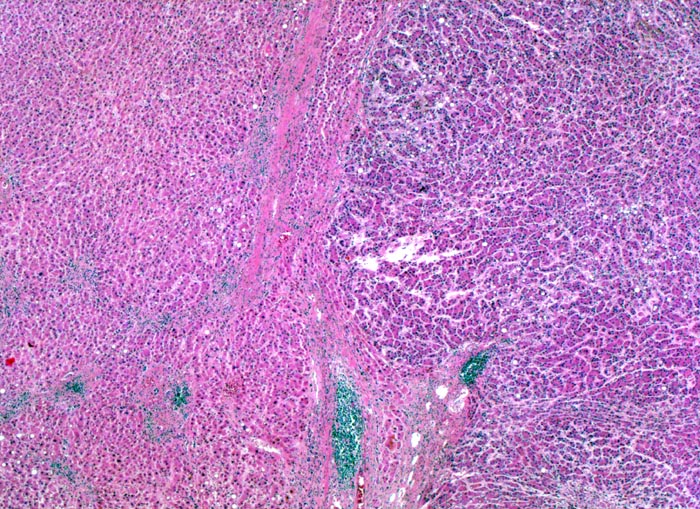

Makroskopisch imponiert das hepatozelluläre Karzinom als solitäre grosse Tumormasse, als zahlreiche zirrhoseartige Knoten oder als scharf begrenzter Knoten mit oder ohne Kapsel. Die tumorfreie Leber ist in der Mehrheit der Fälle zirrhotisch umgebaut. Mikroskopisch bilden die Tumorzellen mehr als 2 Zellen breite Trabekel (> 1237), kompakte Tumormassen (> 1229) oder pseudoglanduläre Strukturen (dilatierte Canaliculi) (> 1212) (> 1199). Desmoplastisches Bindegewebe fehlt meist. Innerhalb des Tumors fehlen Portalfelder. Es finden sich lediglich Arterien. Etwa bei der Hälfte der Karzinome lässt sich intrazytoplasmatische oder intracanaliculäre Galle (> 1238) nachweisen. Immunhistochemisch lassen sich mit einem polyklonalen Antikörper gegen Carcinoembryonales Antigen (CEA) Gallecanaliculi zwischen den Tumorzellen nachweisen. Die Tumorzellen bilden keinen Schleim.

Morphologische Merkmale:

• Scharf begrenzter bekapselter Tumor.

• Innerhalb des Tumors Blutgefässe, aber keine Portalfelder.

• Die Tumorzellen bilden Trabekel, welche überwiegend mehr als 2 Zellen breit sind und Pseudodrüsen.

• Sinusoidartige Blutgefässe mit Endothelauskleidung verlaufen zwischen den Trabekeln und den Pseudodrüsen.

• Die Tumorzellen erinnern an normale Hepatozyten, sind aber kleiner als die Hepatozyten und die Kern-Zytoplasmarelation ist deutlich erhöht. Das Zytoplasma ist basophiler als das der angrenzenden Hepatozyten.

• Galle ist sichtbar in den Pseudodrüsen.

• Tumorfreies Parenchym mit chronischer viraler Hepatitis (B und D): dichtes chronisches Entzündungsinfiltrat in den Portalfeldern übergreifend auf das Parenchym (Interfacehepatitis). Spärliche intralobuläre Entzündung mit Einzelzellnekrosen (Apoptosen). Fibrose der Portalfelder mit Septenbildung und unvollständigem zirrhotischem Umbau.